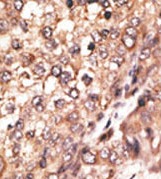

Supportive validation

- Submitted by

- Acris Antibodies GmbH (provider)

- Main image

- Experimental details

- Formalin-fixed and paraffin-embedded human hepatocarcinoma reacted with the primary antibody, which was peroxidase-conjugated to the secondary antibody, followed by DAB staining. This data demonstrates the use of this antibody for immunohistochemistry; clinical relevance has not been evaluated.